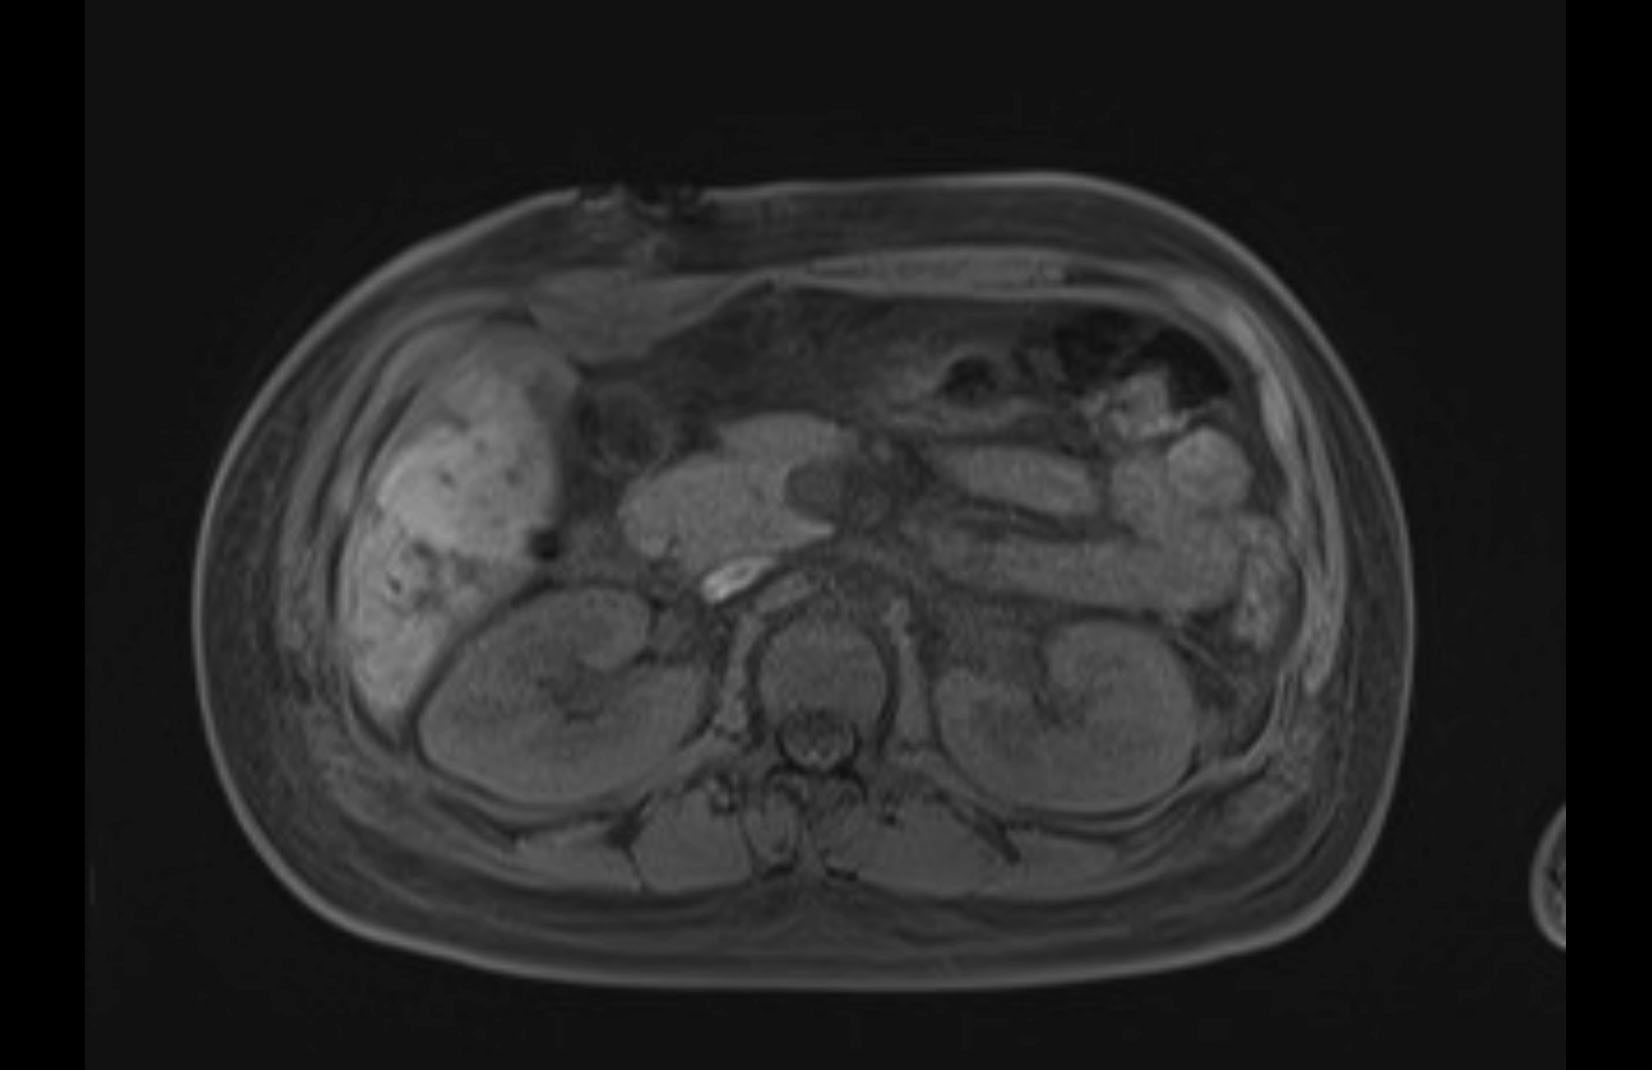

Imaging Analysis

Look through the patient's CT scan to identify any areas of concern for the necessary procedure.

MRI T1

Based on initial findings, which issue(s) would you be most concerned about?